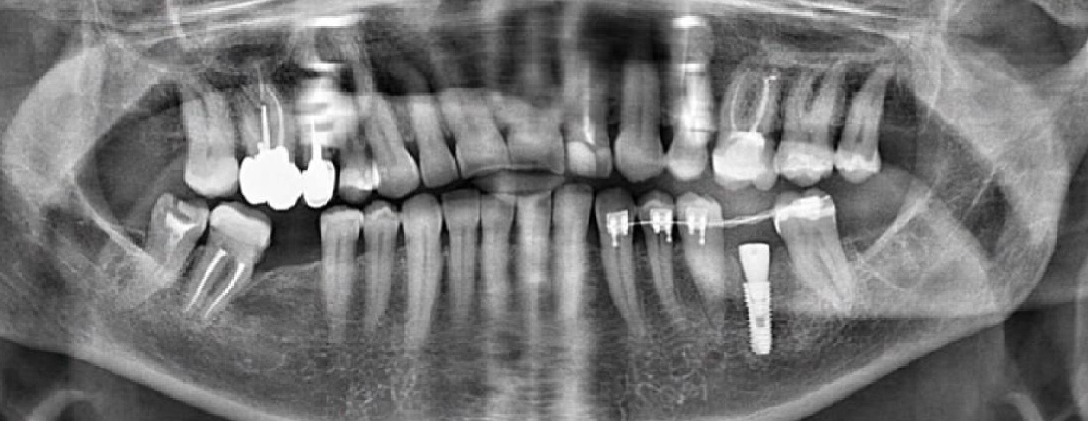

Для примера – клинический случай. Ранее мы установили и запротезировали имплант на нижней челюсти слева. Перед протезированием провели ортодонтическую коррекцию и после зафиксировали коронку.

Примечание: на правой части снимка – левая сторона пациента, а на левой части снимка – правая. Панорамный снимок (он же ОПТГ) всегда перевертыш.

«+» идеальная позиция коронки => лучше гигиена, нет проблем с фиксацией

«–» до сдачи коронки от момента имплантации пришлось ждать более полугода

Поэтому от ортодонтии на правой стороне пациентка отказалась. Что же мы поменяли?

1. Удаление зуба мудрости, седьмого зуба, сразу установка двух имплантов: на место отсутствующего шестого и только что удаленного седьмого зуба (приживление 3 месяца).

ИТОГО: 4-5 месяцев до фиксации постоянной коронки. Экономия трех месяцев.